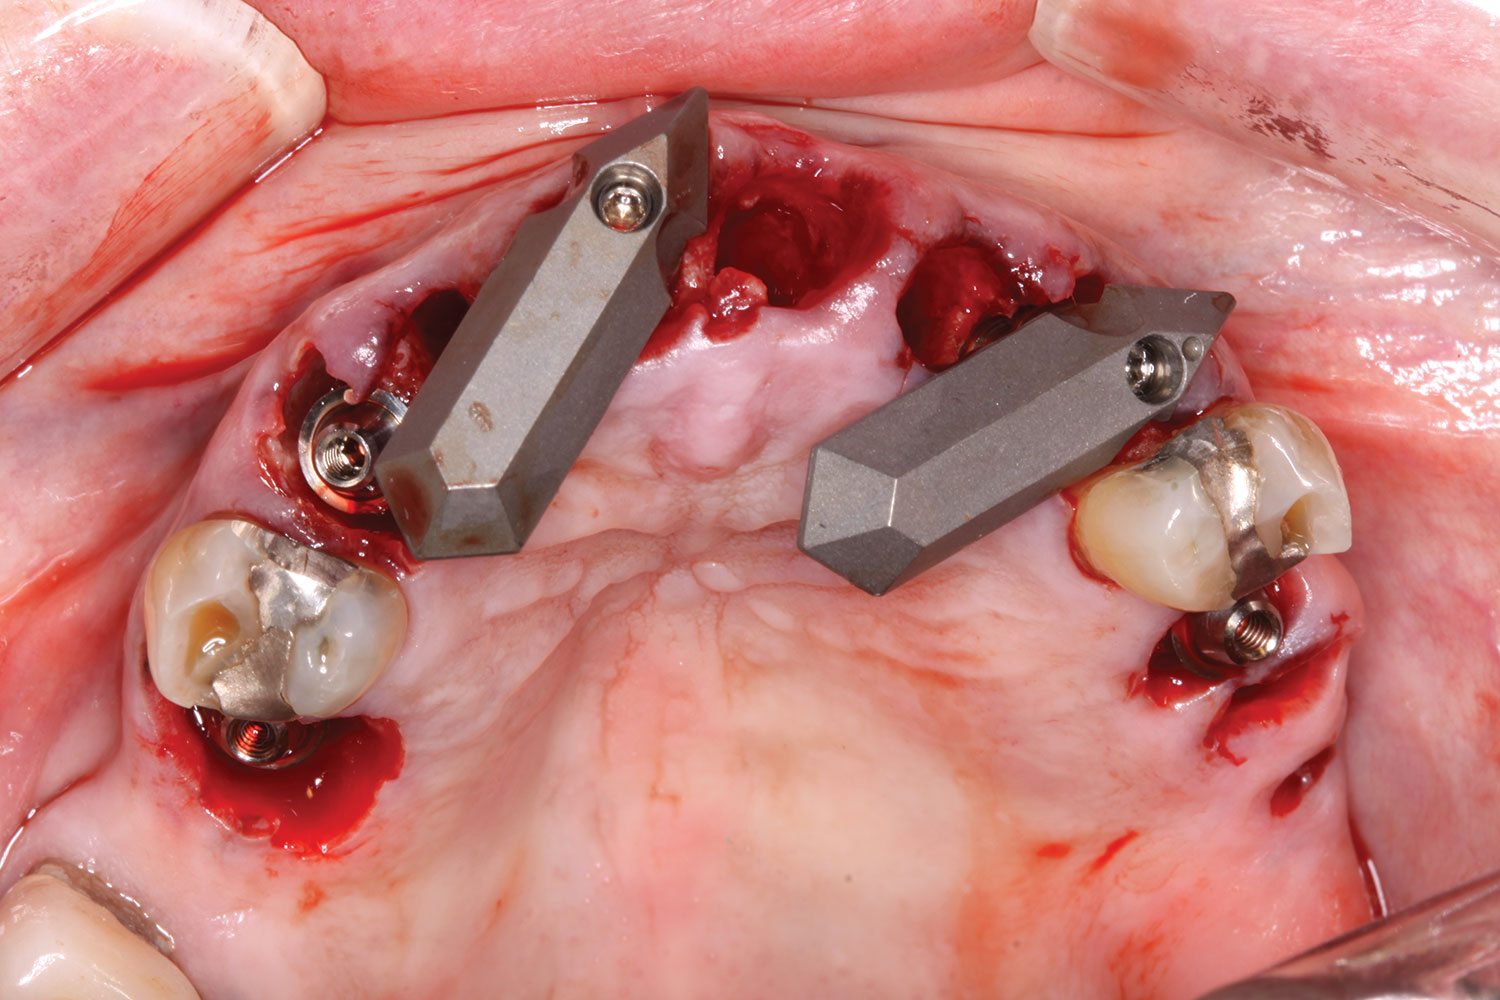

A week later the patient presented for surgery for extraction and replacement of her existing maxillary dentition with implants and a screw-retained provisional implant restoration. Teeth Nos. 2, 4, and 6 through 11, 13, and 14 were carefully extracted with attention paid to retaining site dimensions. Immediate implants were inserted into sites Nos. 4, 6, 8, 11, and 13 with high insertion torques in excess of

40 Ncm. Subsequently, multi-unit abutments were placed on all the implants and torqued to 30 Ncm, and scan gauges were placed on implant Nos. 8 and 11 (Figure 12 and Figure 13).

A maxillary intraoral scan was obtained with a digital scanner capturing the two remaining teeth in sites Nos. 5 and 12 and the scan gauges on implants Nos. 8 and 11. Subsequently, teeth Nos. 5 and 12 were extracted. Scan gauges were placed on implants Nos. 4, 6, and 13. At this time, another intraoral scan was captured of all the scan gauges on the five implants with the surrounding soft tissues (Figure 14 and Figure 15).